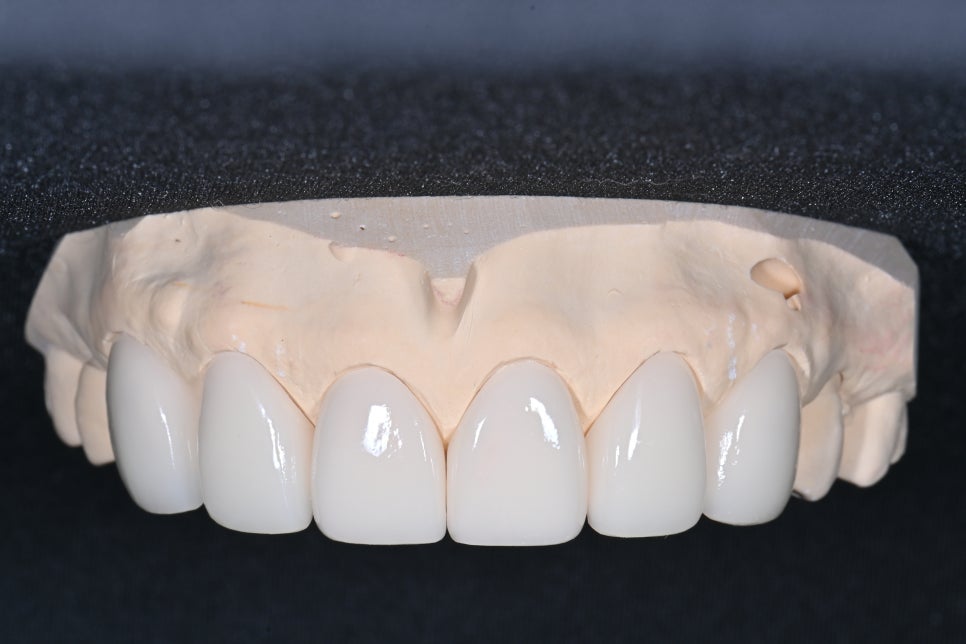

환자 구강 환경에 맞는

맞춤형 라미네이트

들어간 치아 부분을 무삭제 라미네이트를

이용하여 입술 쪽의 볼륨감을 주기 위해

라미네이트가 제작되었습니다

치아 석고모델에서 완성된 라미네이트입니다

각각 필요한 부분에 따라 0.1mm 정도의 얇은 층과

볼륨감을 위해 두께감이 필요한 곳은 충분한 두께로

제작되었습니다

천편일률적으로 생긴 라미네이트가 아닌

각 치아 형태에 맞춰 곡선을 갖는 라미네이트가 필요합니다.

처음 왔을 때 각진 치아 형태에서

잇몸 선을 따라 여성형의 치아 형태를 만든 형태입니다